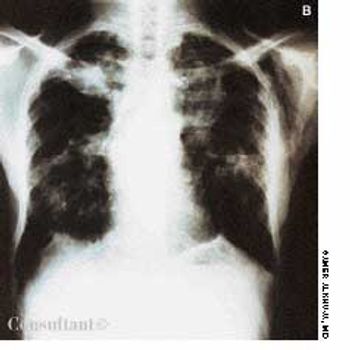

A 2 1/2-year-old child is hospitalized with a 1-month history of worsening persistent cough. She was initially treated with a 5-day course of oral amoxicillin, and her symptoms abated somewhat. However, for the past week, she has experienced high fever and chills associated with right-sided pleuritic chest pain.

The diagnosis of cystic fibrosis (CF) is typically made in childhood. However, there is increasing evidence that a mild and atypical form of this disease can present in adulthood. The author describes a patient who received the diagnosis of CF when she was 74 years old.

Abstract: In addition to causing pulmonary disease, infection with Mycobacterium tuberculosis can result in a wide range of extrapulmonary manifestations, including abdominal involvement. Patients with acute tuberculous peritonitis typically present with fever, weight loss, night sweats, and abdominal pain and swelling. Intestinal tuberculosis is characterized by weight loss, anorexia, and abdominal pain (usually in the right lower quadrant). A palpable abdominal mass may be present. Patients with primary hepatic tuberculosis may have a hard, nodular liver or recurrent jaundice. The workup may involve tuberculin skin testing, imaging studies, fine-needle aspiration, colonoscopy, and peritoneal biopsy. Percutaneous liver biopsy and laparoscopy are the main methods of diagnosing primary hepatic tuberculosis. Treatment includes antituberculosis drug therapy and, in some cases, surgery. (J Respir Dis. 2005;26(11):485-488)